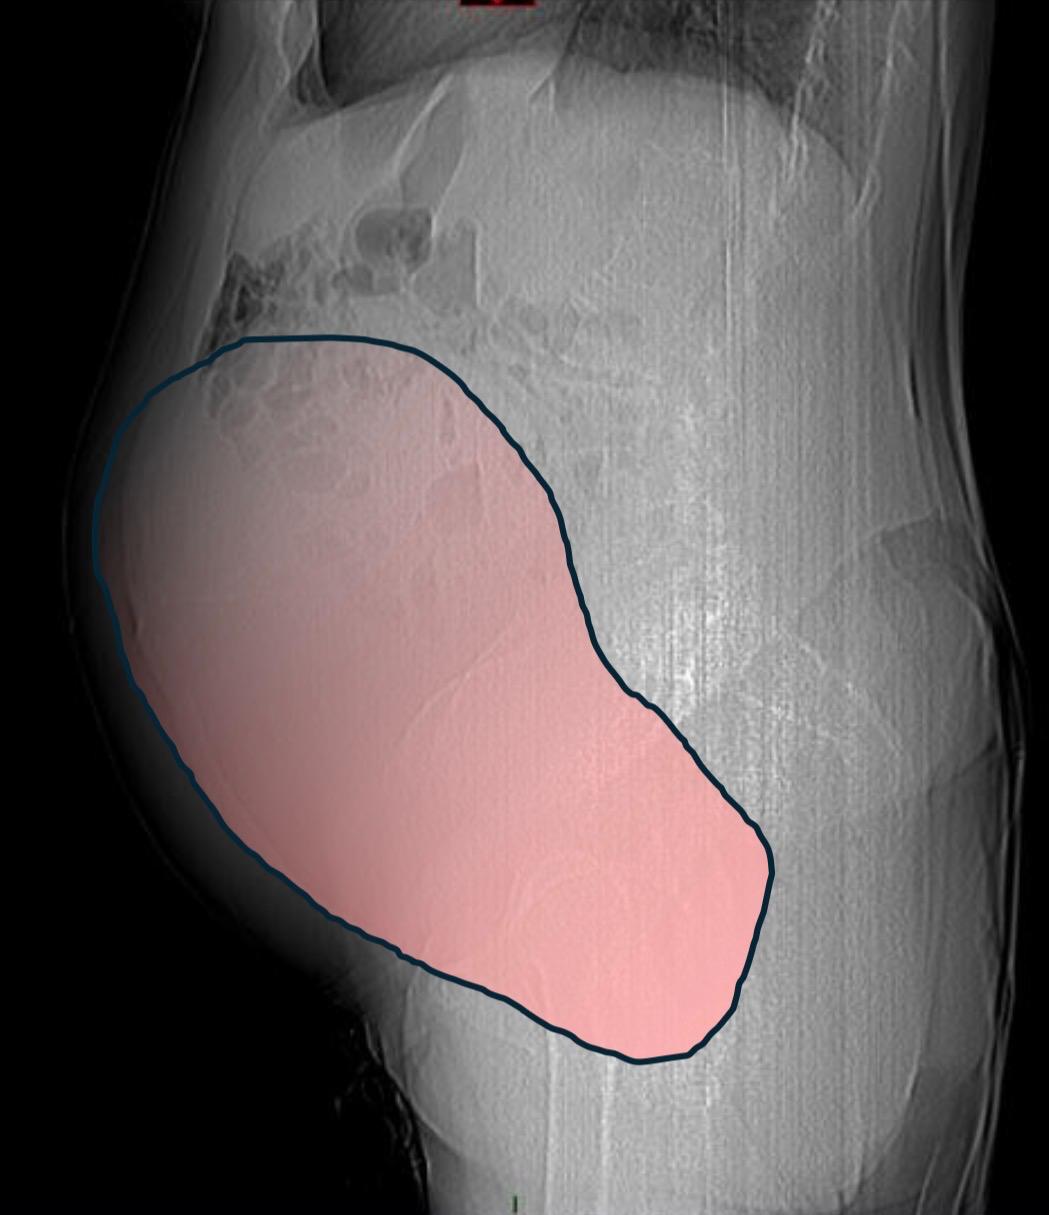

Per mesi la gigantesca cisti ovarica, con un diametro di circa 28 centimetri, è rimasta nascosta, senza dare segnali evidenti. La paziente non si era accorta di nulla. L’allarme è scattato quando la massa, associata alla presenza di una seconda neoplasia intestinale, ha iniziato a comprimere il colon, provocando sintomi acuti ed improvvisi fino ad una grave difficoltà intestinale non più ignorabile.

Durante l’intervento emerge tutta la gravità della situazione. La gigantesca neoplasia ovarica viene asportata: pesa circa 6 chilogrammi, con un volume paragonabile a quello di una gravidanza gemellare a termine. Ma non è l’unica minaccia. I sintomi più pericolosi sono legati alla sofferenza intestinale, che richiede un intervento immediato e coordinato di più specialisti.